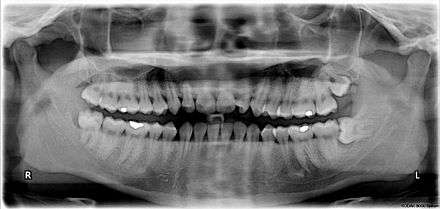

A wisdom tooth or third molar is one of the three molars per quadrant of the human dentition. It is the most posterior of the three. Wisdom teeth generally erupt between the ages of 17 and 25.[1] Most adults have four wisdom teeth, one in each of the four quadrants, but it is possible to have fewer or more, in which case the extras are called supernumerary teeth. Wisdom teeth commonly affect other teeth as they develop, becoming impacted. They are often extracted when this occurs.

Wisdom teeth (often notated clinically as M3 for third molar) have long been identified as a source of problems and continue to be the most commonly impacted teeth in the human mouth. The oldest known impacted wisdom tooth belonged to a European woman of the Magdalenian period (18,000–10,000 BCE).[5] A lack of room to allow the teeth to erupt results in a risk of periodontal disease and dental cavities that increases with age.[6] Less than 2% of adults age 65 years or older maintain the teeth without cavities or periodontal disease and 13% maintain unimpacted wisdom teeth without cavities or periodontal disease.[7]

Impacted wisdom teeth are classified by the direction and depth of impaction, the amount of available space for tooth eruption and the amount soft tissue or bone that covers them. The classification structure allows clinicians to estimate the probabilities of impaction, infections and complications associated with wisdom teeth removal.[6] Wisdom teeth are also classified by the presence of symptoms and disease.[8]